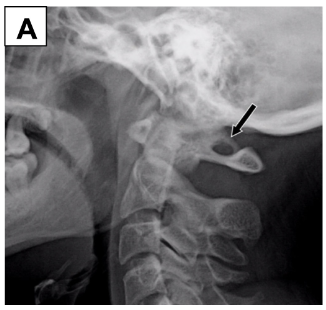

Se presentan dos pacientes, un varón de 35 años (A) y una mujer de 32 años (B), con cervicalgia crónica. En la radiografía lateral de columna cervical se encontró un puente óseo sobre el agujero de la arteria vertebral C1, característico de pontículus posticus. Se postula que el pontículus posticus surge de la osificación del segmento lateral del ligamento atlanto occipital superior, siendo unilateral o bilateral. Puede ser un hallazgo imagenológico incidental en un paciente asintomático; sin embargo, puede provocar isquemia vertebro-basilar, vértigo, cervicalgia y cefalea. Entre los hallazgos, en la radiografía lateral de cuello se evidencia una calcificación parcial o completa sobre el techo óseo del agujero de la arteria vertebral C1, tal como se encontró en ambos casos, por lo que es importante tener en cuenta este hallazgo e informarlo en pacientes que cursen con algunos de los síntomas descritos.

We present two patients, 35-year-old male (A) and 32-year-old woman (B), with chronic cervicalgia. On whose lateral radiograph of the cervical spine demonstrates an osseous roof over the C1 vertebral artery foramen, characteristic of ponticulus posticus. Ponticulus posticus arises from ossification of the lateral segment of posterior atlantooccipital ligament, being unilateral or bilateral. It may be an incidental imaging finding in an asymptomatic patient; however, it can cause vertebrobasilar ischemia, vertigo, neck pain and headache. The lateral neck x-ray usually shows a partial or complete osseous roof over C1 vertebral artery foramen, as shown as in both cases, so it is important to take this finding into account and report it in patients with some of the symptoms described.